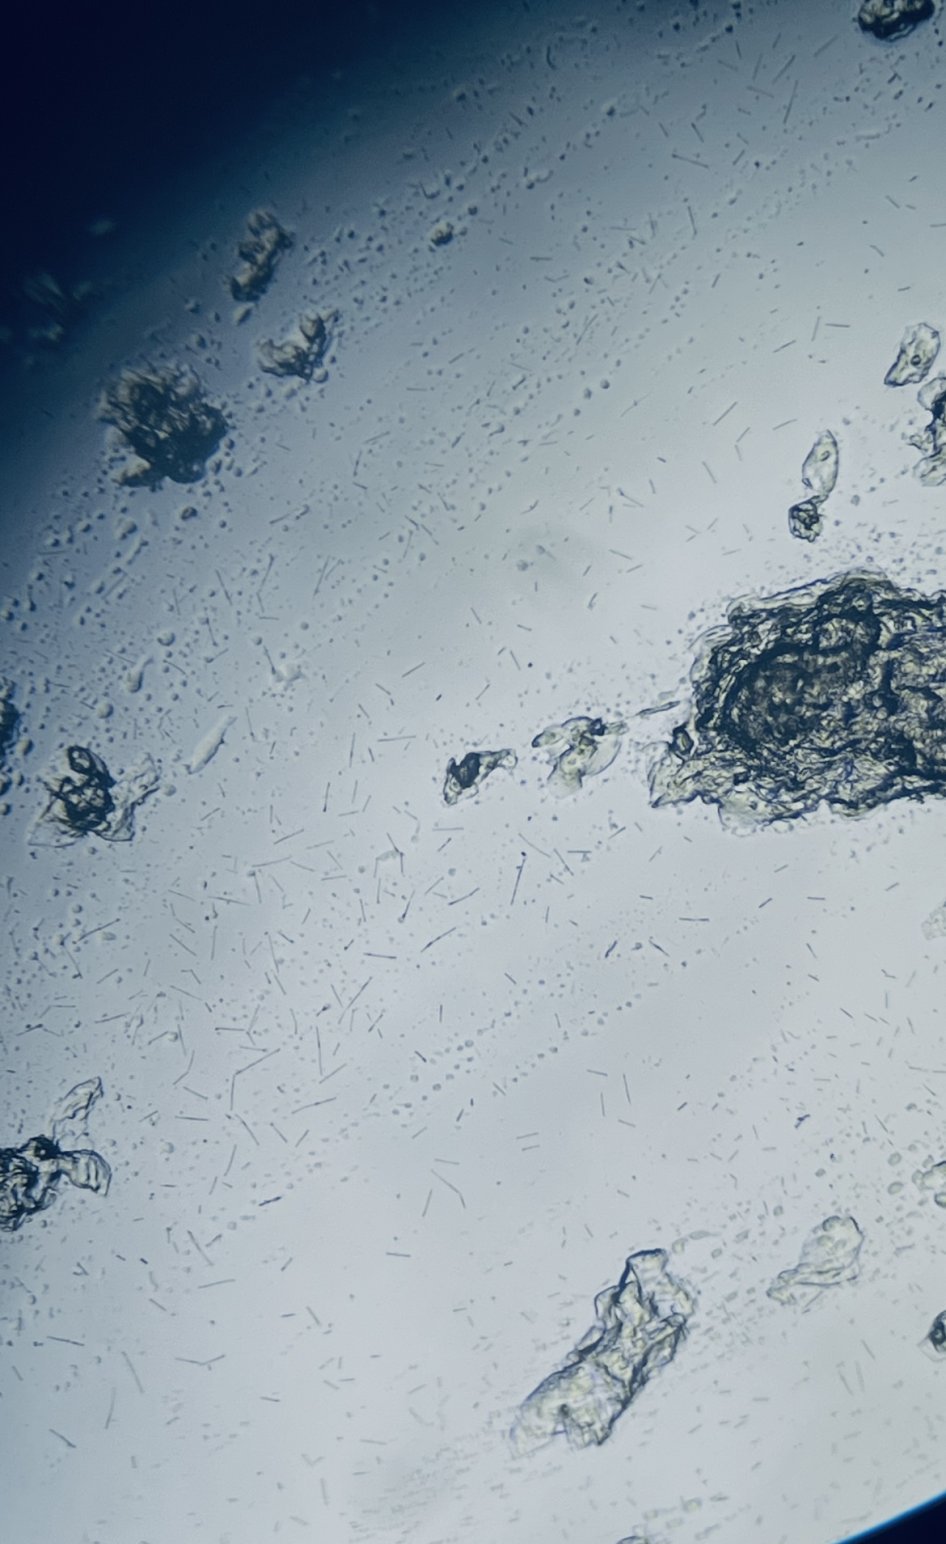

На снимката в дясно черното кълбо е биофилм на гарднерела а ситните пръчки , като косъмчета са Цитробактера.